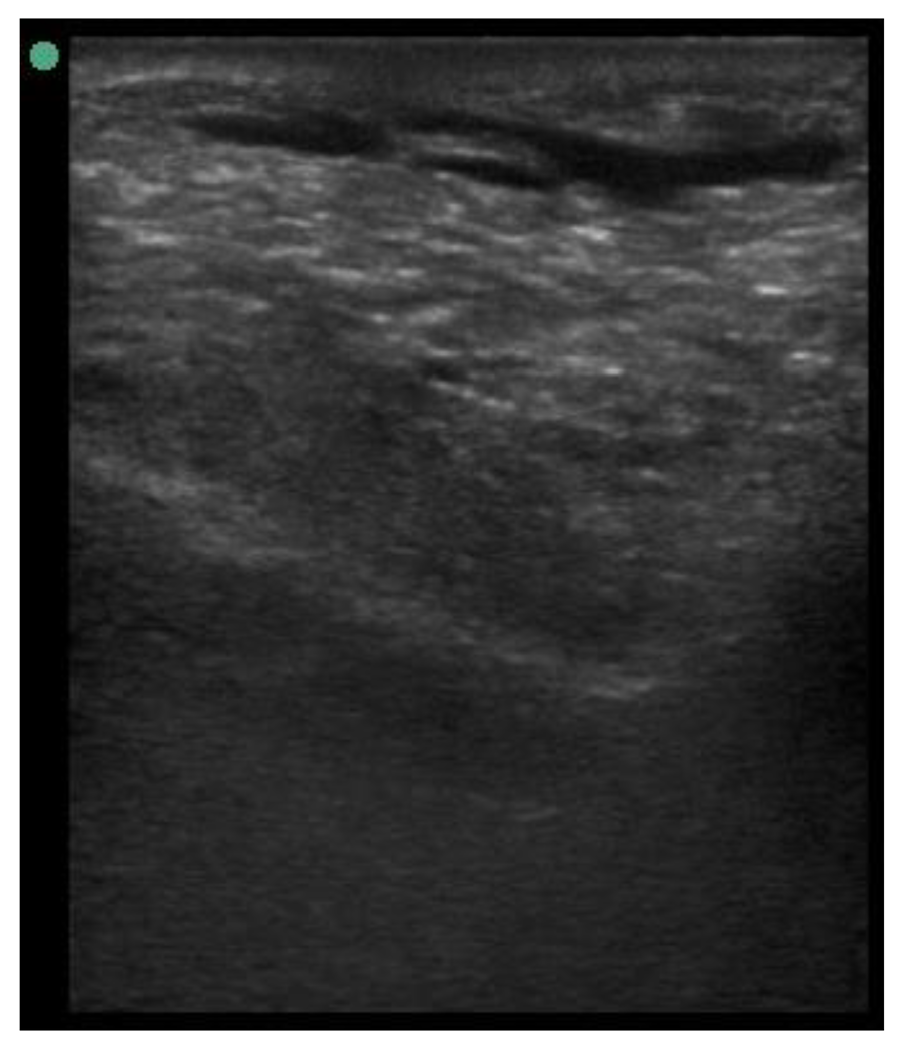

| 113 days of pregnancy (P113) Scanning depth 4.7 cm | ![]() | ![]() | MT generous: 28.9 mm MT conservative: 25.9 mm Gland cistern: 3.3 mm Parenchyma: 10.9 mm Fat Pad: 10.0 mm |